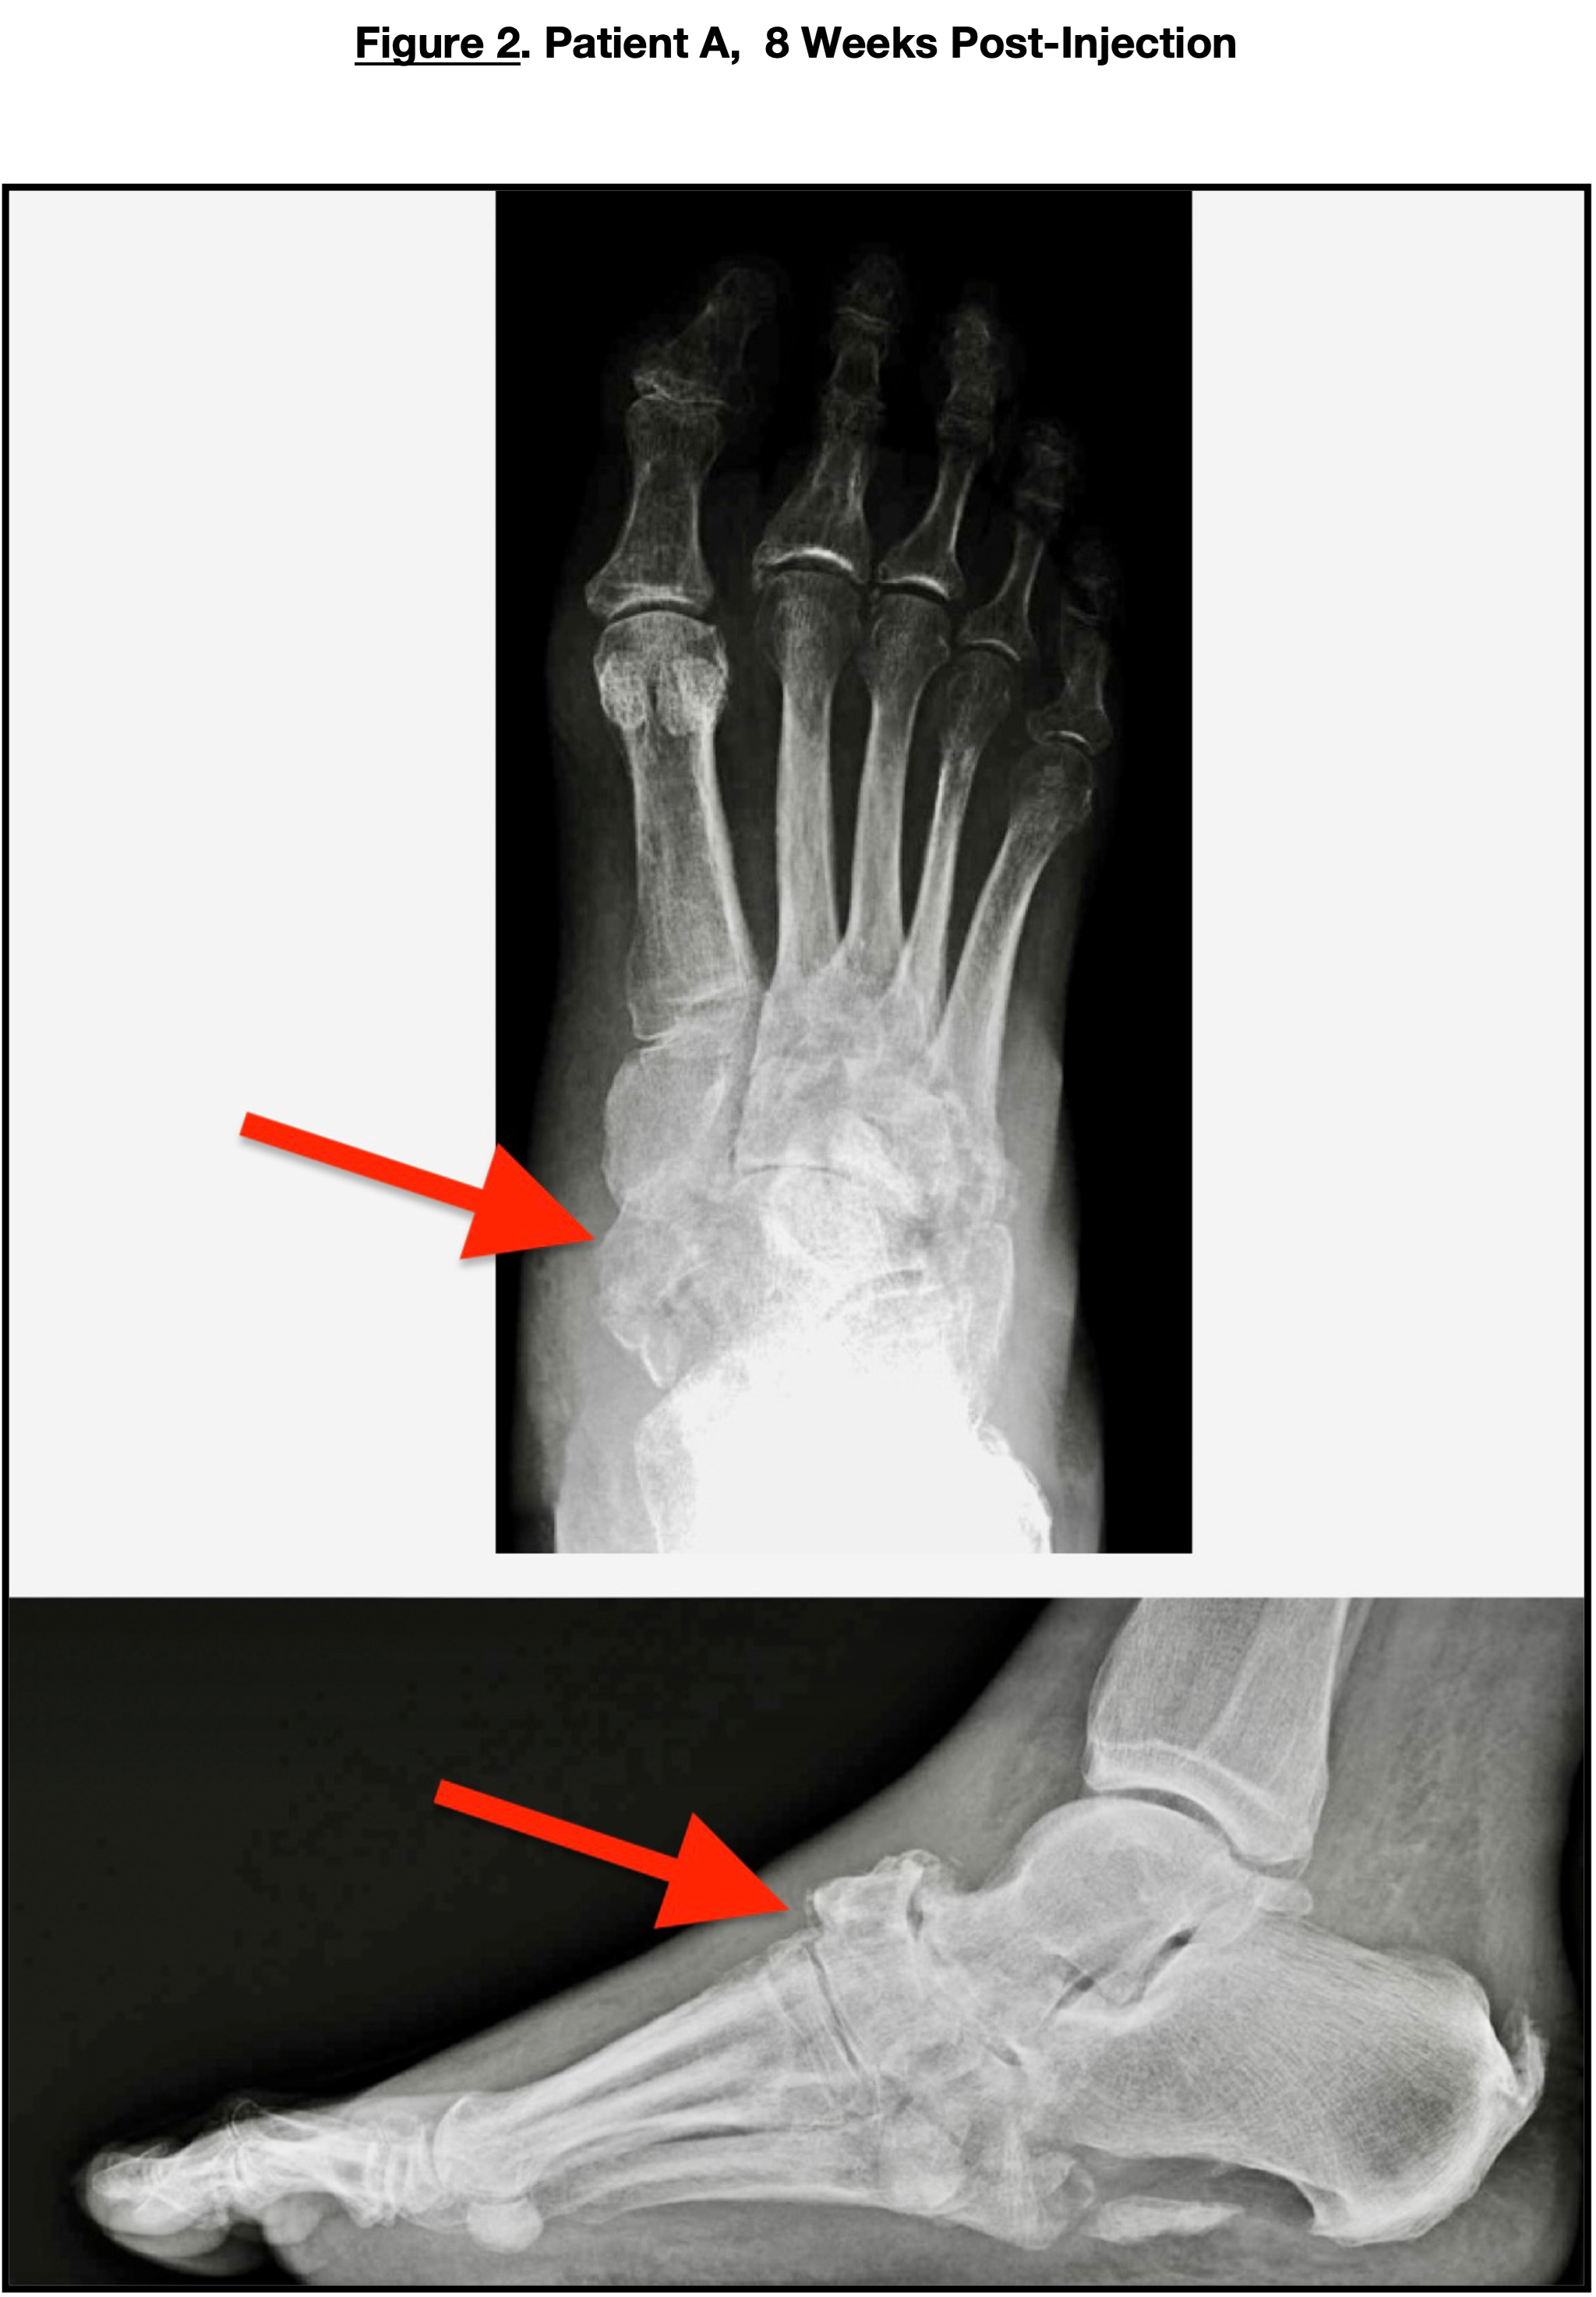

After confirming no acute infectious process, the patient underwent placental tissue injections into the midfoot fracture areas in the clinic setting. She was placed in a controlled ankle motion (CAM) boot for 4 weeks. She was seen 2 weeks, 6 weeks, and 8 weeks post-injection. The erythema and calor had subsided, and there was radiological evidence of microfracture consolidation. An 8-week follow-up X-ray (Figure 2) revealed continued calcification and consolidation. Follow-up C-reactive protein was 6 mg/dL. The patient then transferred into an extra-depth shoe with appropriate plastizote inserts for full weight-bearing.